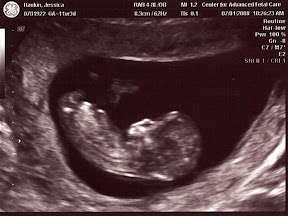

This is a long awaited and greatly prayed for moment for all of us. We have been very excited and God has shown us so much mercy as the pregnancy has progressed. We saw the heartbeat at that first ultrasound which gave us confidence in the blessing the Lord has bestowed upon us. At our first Dr.'s appointment, 8 weeks, this baby had the earliest heartbeat our Dr. has ever heard externally with a doppler, another glorious mercy given to us. And then yet again at the 11 week mark the ultrasound revealed that we have been blessed with a healthy baby.

It was such a relief to see the miracle of life, perfectly created by God inside mommy. Though we know that every child is perfectly designed by God, we were very thankful to hear that he had blessed us with a healthy baby. Mom is doing great and the Dr. has said this is a textbook, perfect pregnancy! Praise be to God.